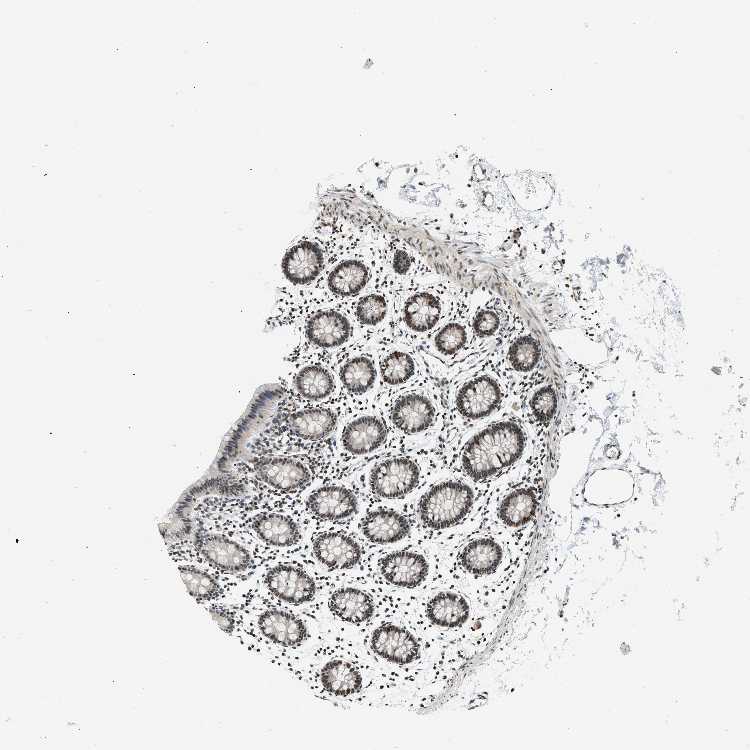

COLON - Antibody stainingi

Antibody staining in the annotated cell types in the current human tissue is reported as not detected, low, medium, or high, based on conventional immunohistochemistry profiling in selected tissues. This score is based on the combination of the staining intensity and fraction of stained cells.

Each image is clickable and will lead to virtual microscopy that enables deeper exploration of all samples and also displays staining intensity scores, fraction scores and subcellular localization as well as patient and tissue information for each sample.

Antibody CAB017544

Endothelial cells High

Glandular cells Medium

Peripheral nerve/ganglion Medium